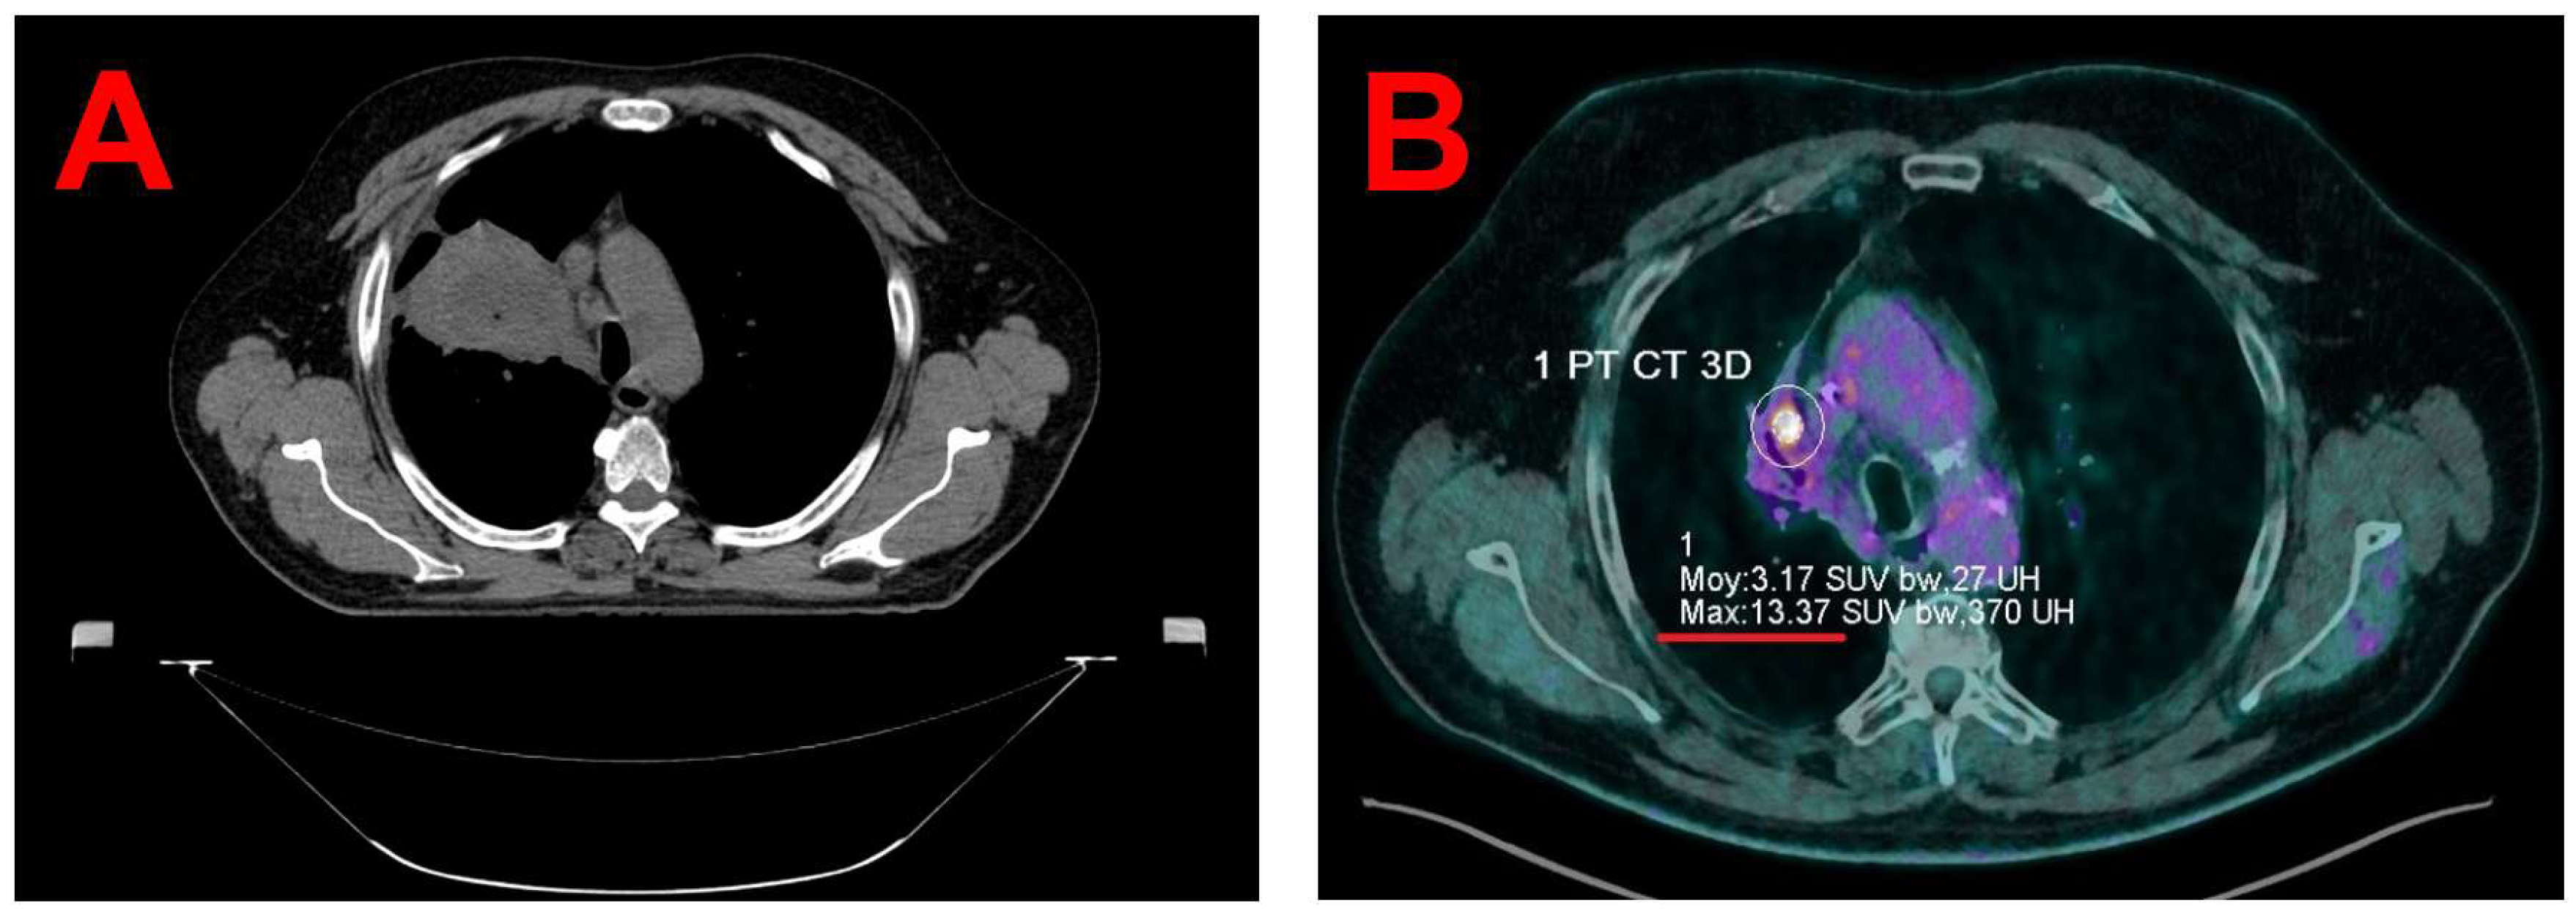

Written informed consent was obtained from the patient for the publication of this case report and accompanying images. The patient is a 67-year-old male (1.70 m, 108 kg) who was diagnosed in 2020 with squamous cell carcinoma of the right upper lobe. Treatment included concurrent chemoradiotherapy (Carboplatin-Paclitaxel, 4 cycles, 66 Gy in 33 fractions; see Figure 1A), followed by immunotherapy with Durvalumab for two years. A PET/CT scan on October 23, 2023, revealed progression of a hypermetabolic focus in the right upper lobe (maximum Standardized Uptake Values (SUVmax) 9.8 vs. 4.7 in January 2023), indicating a suspected local recurrence. A multidisciplinary tumor board on November 2, 2023, recommended SBRT and Nivolumab. A subsequent PET/CT scan on December 7, 2023, showed a further increase in metabolic activity, with a maximum SUVmax of 13.4 (see Figure 1B).

Figure 1. Axial view from the planning CT of the initial 2020 radiotherapy treatment showing extensive infiltration of the squamous cell carcinoma in the right upper lobe (A) and axial view from the December 07, 2023, follow-up PET/CT showing progression of a residual para-mediastinal hypermetabolic focus located within a region of extensive radiation-induced fibrosis in the right upper lobe (SUVmax 13.4 vs. 4.7 in January 2023) (B).